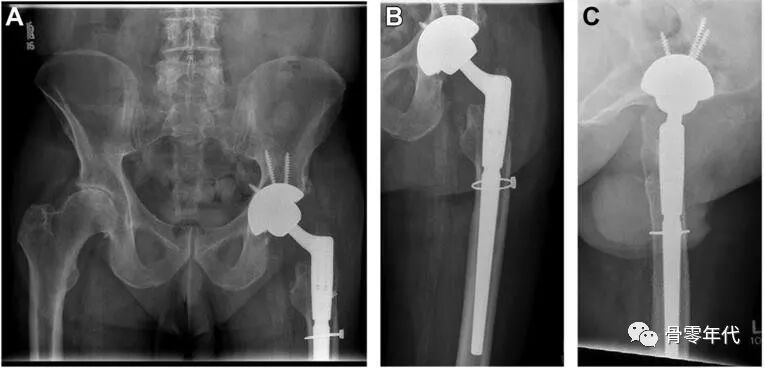

(A-C)术前X光显示左侧股骨近端骨量减少,翻修时预先放置的模块化骨干接合股骨柄用于假体周围骨折的治疗。(D和E)在外展肌重建前进行的MRI图像显示臀中肌和小肌脂肪萎缩,股骨肌腱附着处改变。(F和G)外展肌重建18个月后的部分MRI图像显示臀中肌附着完整,臀小肌部分连续。患者报告的外展肌重建术23个月的结果包括:静息疼痛,1/10;行走疼痛,3/10;Harris髋关节评分,61;牛津髋关节评分,22。患者报告中度跛行,仅需长时间步行时需要拐杖。

(A-C)术前X光显示大转子有轻微骨折,和先前植入的右全髋关节假体,包括非骨水泥的股骨柄和非骨水泥的髋臼假体。(D和E)在外展肌重建前进行的MRI图像显示臀中肌腱仍然附着在大转子骨折片段上。这块骨折碎片已经移位,近端移位。臀小肌腱终止于股骨近端的软组织。外展肌重建术后18个月的报告包括:休息疼痛,3/10;行走疼痛,8/10;Harris髋关节评分,26;牛津髋关节评分,37。患者报告中度跛行,行走时使用助行器。